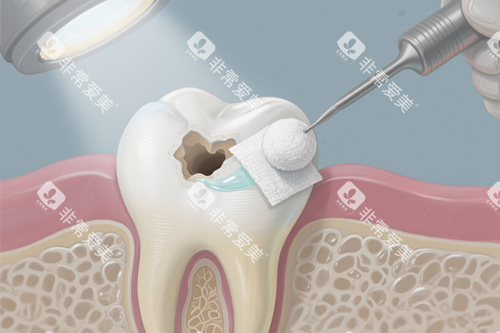

嵌体通过定制修复体嵌入牙体,密合度远高于直接充填,适用于牙体缺损较大或对咬合功能要求高的患者。其价格因材料工艺差异显著。

采用椅旁CAD/CAM技术快速制作,适合后牙功能修复,但长期耐磨性弱于陶瓷。

嵌体需制取牙体模型、智能化设计、车间加工,流程复杂度高于直接补牙。若选择品牌加工厂(如德国威兰德氧化锆),费用可能上浮30%-50%。

嵌体制作需医生、技师、设备三方协作,单颗嵌体操作时间约1-2小时,是直接补牙的3-5倍;前牙美学修复对医生色彩匹配能力要求更高,费用相应增加。